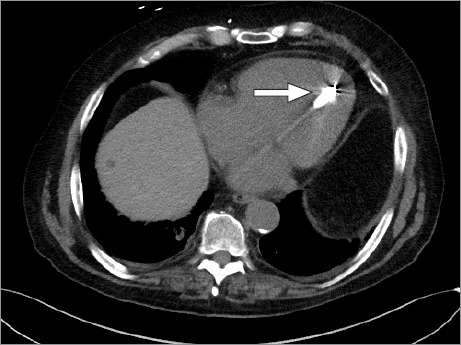

Micra装置是一种通过股静脉经导管入路植入右心室的无铅起搏器。使用无导线起搏器有几个适应症和优点,该设备在心脏病学领域的作用可能会继续增加。这篇文章提出了一个罕见的并发症的情况下,可能是由于无意中放置装置在左心室跨越一个未确诊的卵圆孔未闭。

The Micra device is a leadless pacemaker implanted in the right ventricle via a femoral vein transcatheter approach. There are several indications for and advantages to using a leadless pacemaker, and the device's role in the field of cardiology will probably continue to increase. This article presents the case of a rare complication probably due to inadvertent placement of the device in the left ventricle across an undiagnosed patent foramen ovale.